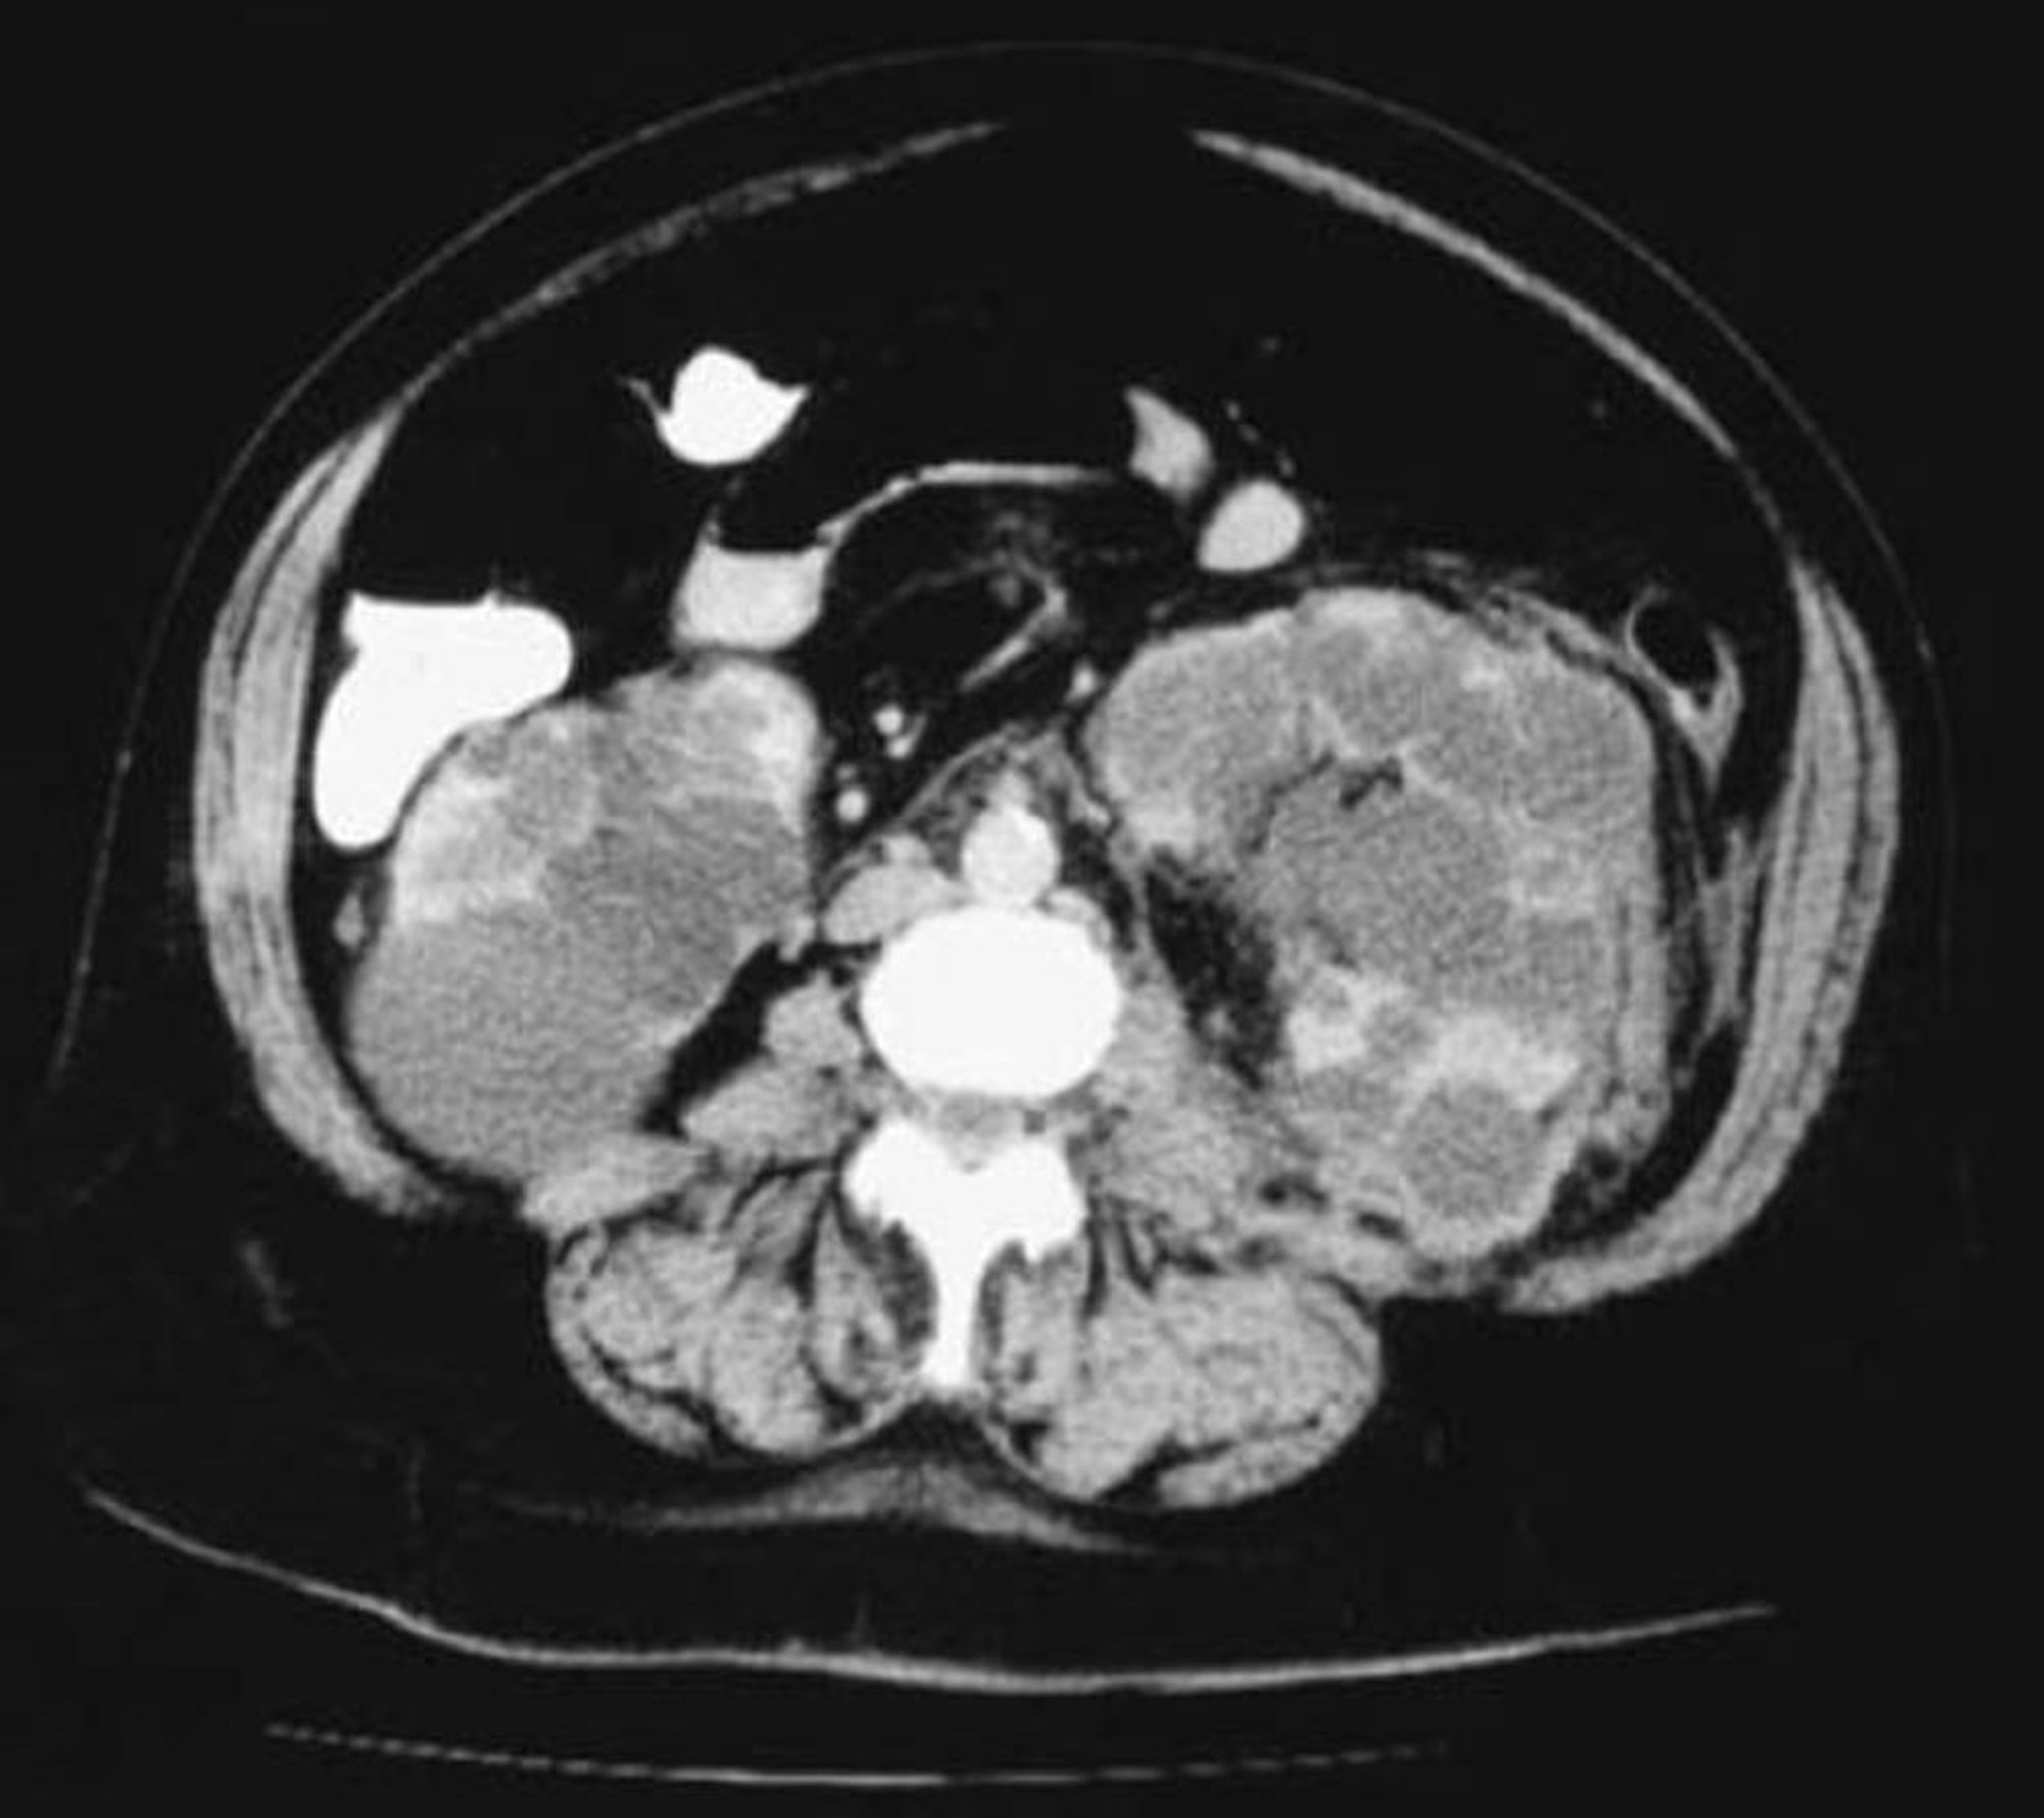

Осевая проекция КТ при поликистозе почек

Эта КТ почек показывает многочисленные кисты различных размеров. Почечной паренхимы почти не осталось.